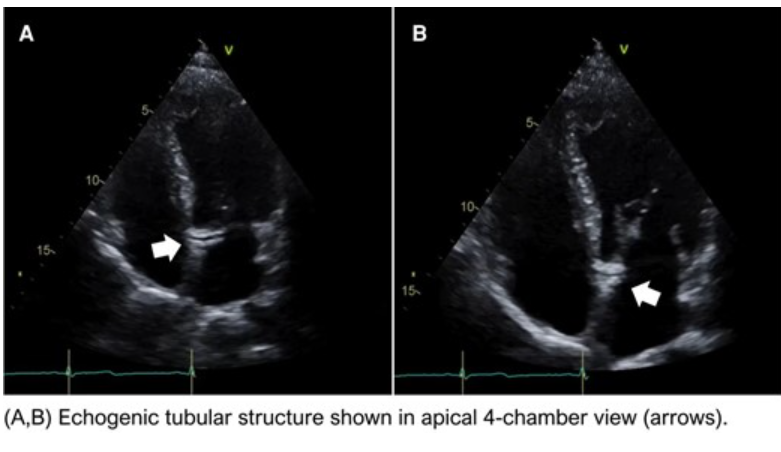

No alt

A 44-year-old man with a history of hypertension and smoking arrived at the emergency department with a 2-day history of oppressive chest pain associated with diaphoresis and nausea. Physical examination revealed high blood pressure (170/100 mmHg) and no signs of heart failure. Serial 12-lead electrocardiogram showed dynamic changes of T wave in V5 and V6, and high-sensitivity cardiac troponin levels were increased (443 ng/mL). Point-of-care ultrasound (POCUS) was performed at the bedside showing the following findings:

What is the likely aetiology of this patient’s chief complaint?

• Coronary sinus calcification

• Retroaortic coronary artery

• Septal communication

• Intra-myocardial dissection